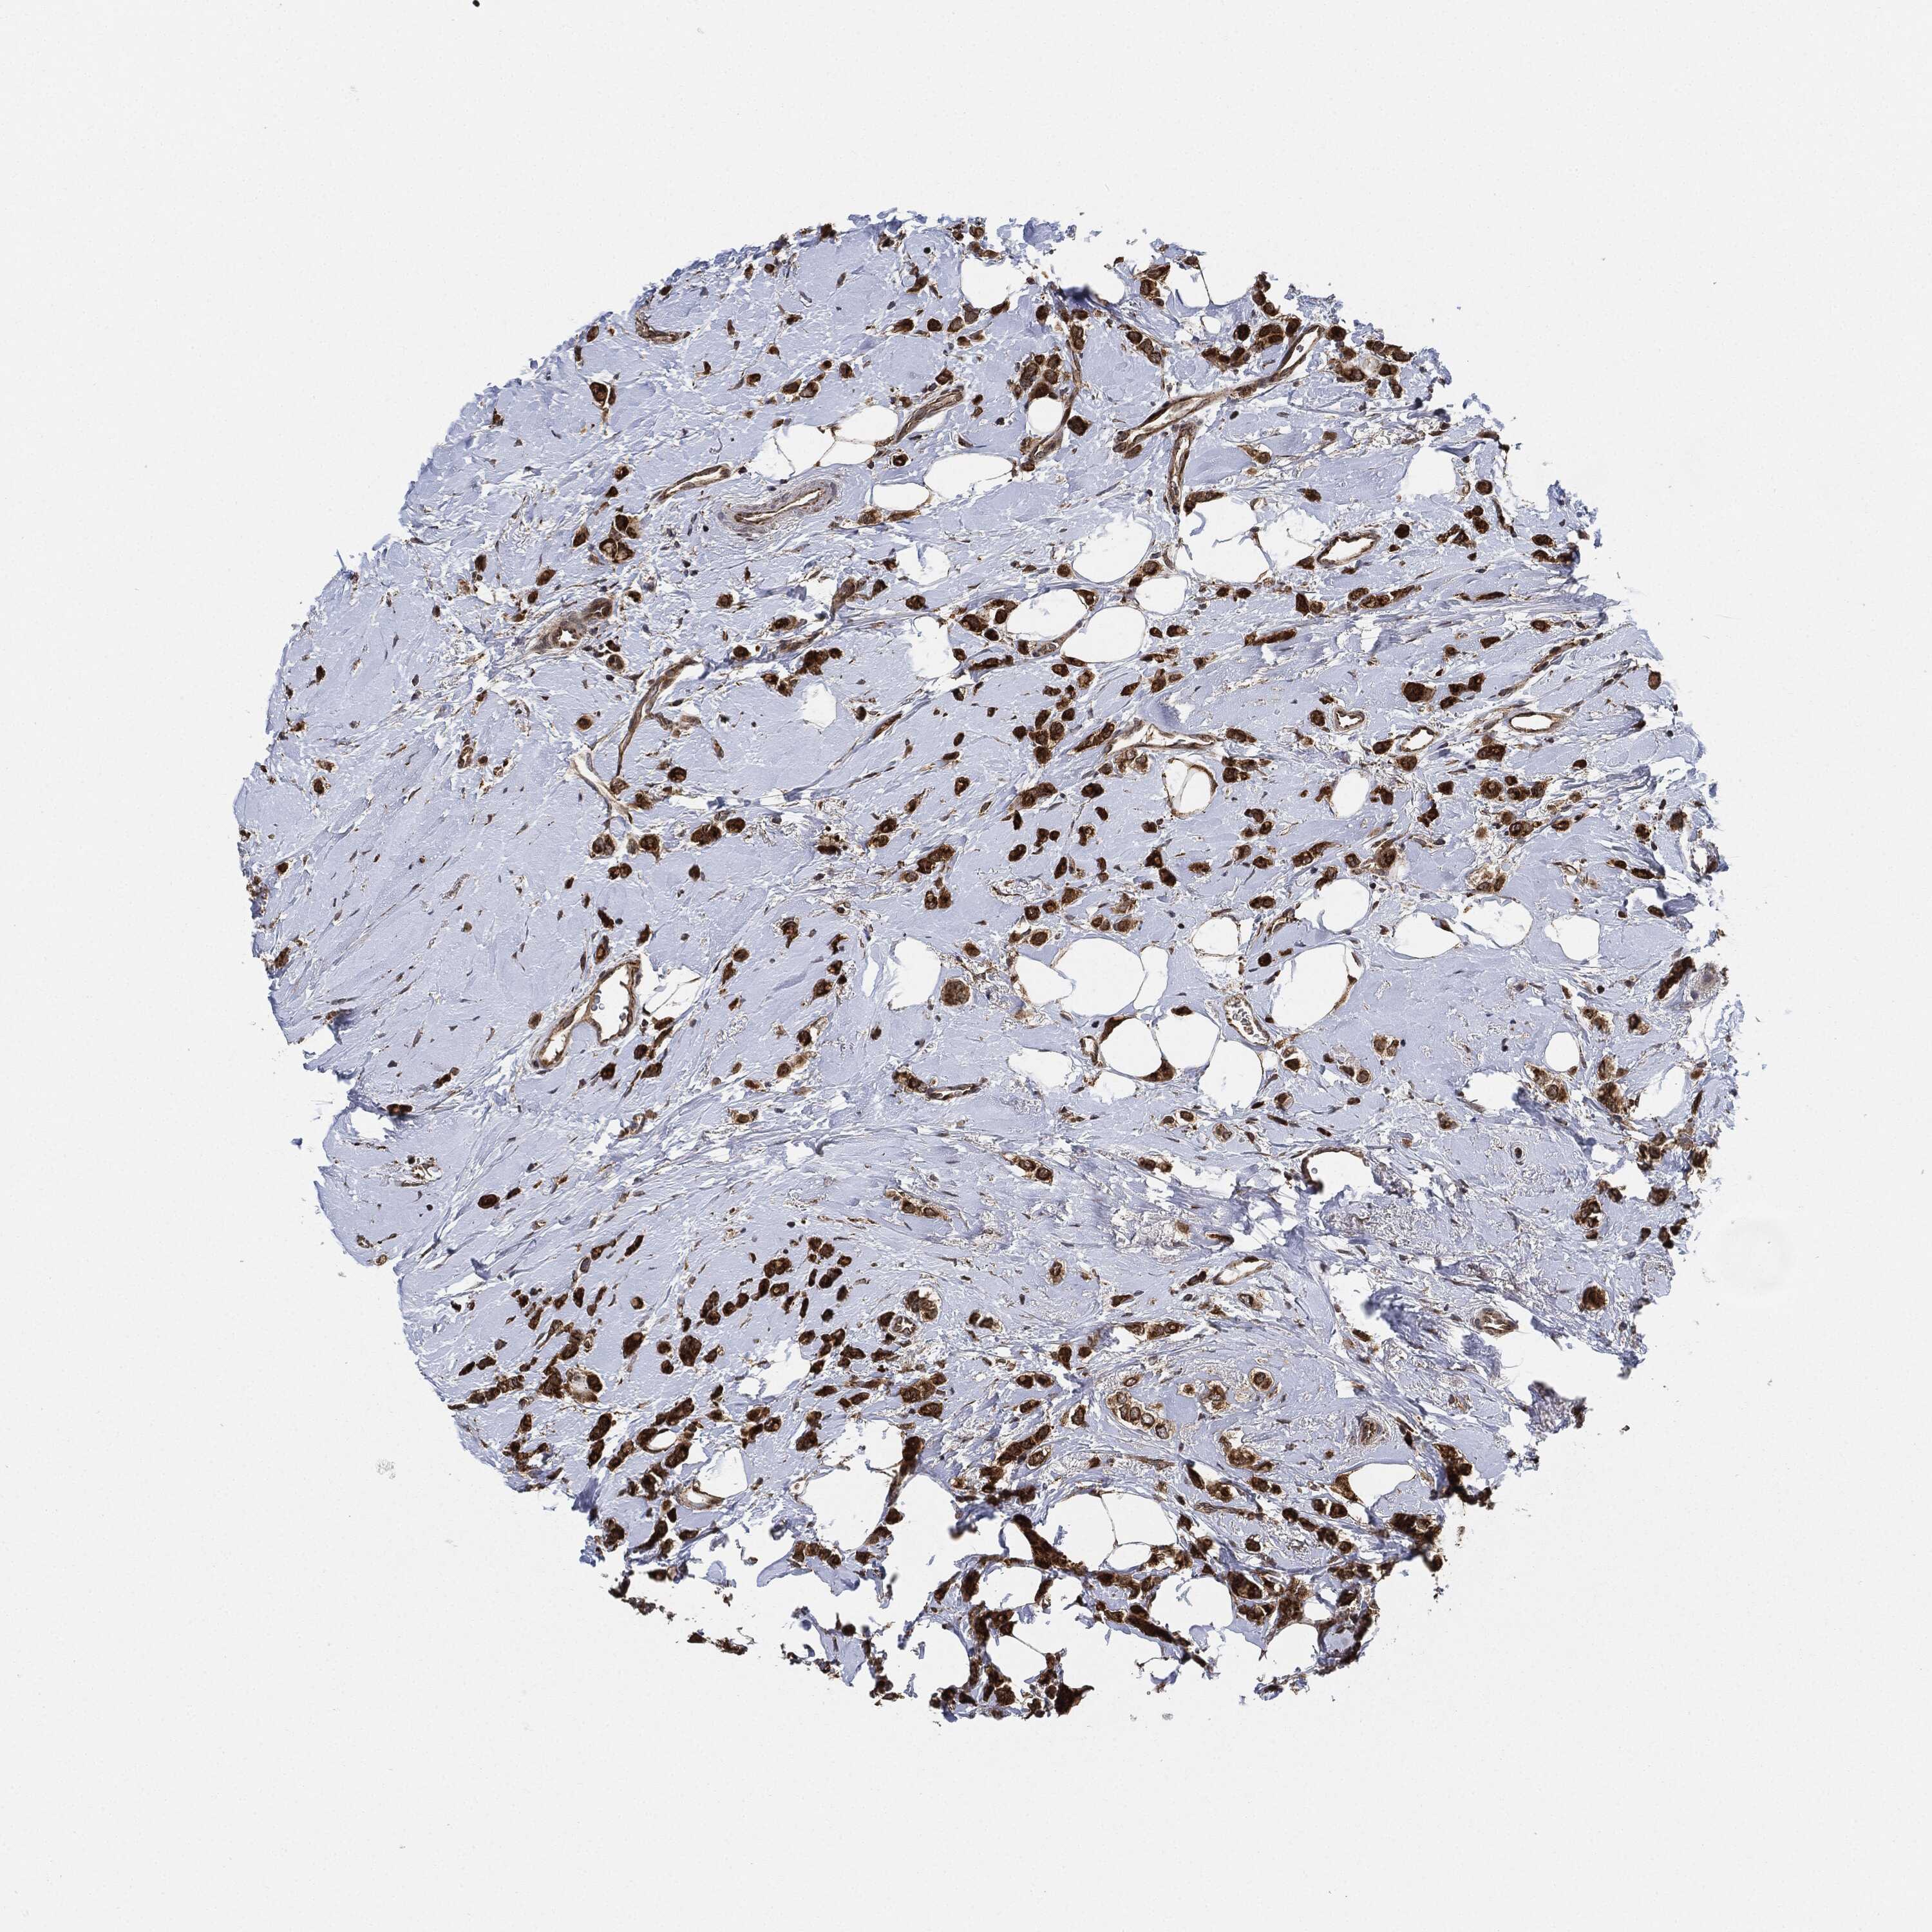

BRCA TCGA BRCA VALIDATION PROTEIN EXPRESSION

ANTIBODIES

AND

VALIDATION